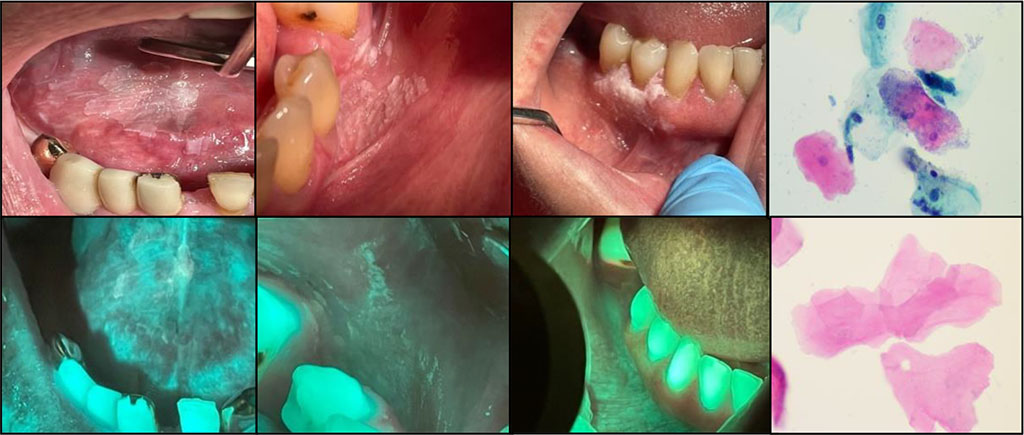

The optical image of oncological diseases is characterized by a complete loss of luminescence - a “dark spot” against the background of the unchanged OM, showing clear boundaries (Fig. 5). In addition, there were some cases presenting no clinical manifestations in the oral cavity (Fig. 6). However, in some cases, the boundaries of the lesion significantly prevailed over the clinical boundaries of the pathological process.

Fig

5a Buccal mucosa malignant neoplasm of the left cheek

5b Optical image of oncology

6a Oncology of the floor of the mouth

6b Optical image of oncology